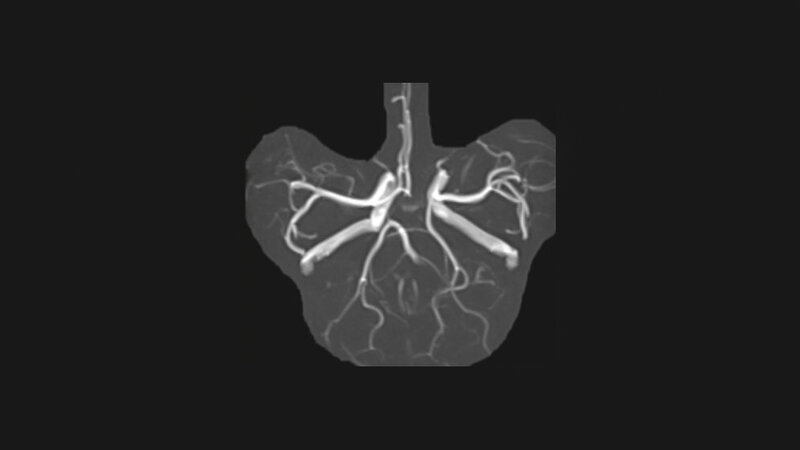

Die symmetrische zirkuläre Konfiguration des Circulus arteriosus cerebri kommt nur in 42,1 % (bei Erwachsenen) vor. Der Hauptunterschied zwischen der fetalen und erwachsenen Anlage ist der Gefäßdurchmesser des Ramus communicans posterior.

The symmetrical, circular configuration of the circulus arteriosus cerebri is present in only about 42,1 % (in adults). The main differences between the fetal and adult disposition is the diameter of the posterior communicating artery.